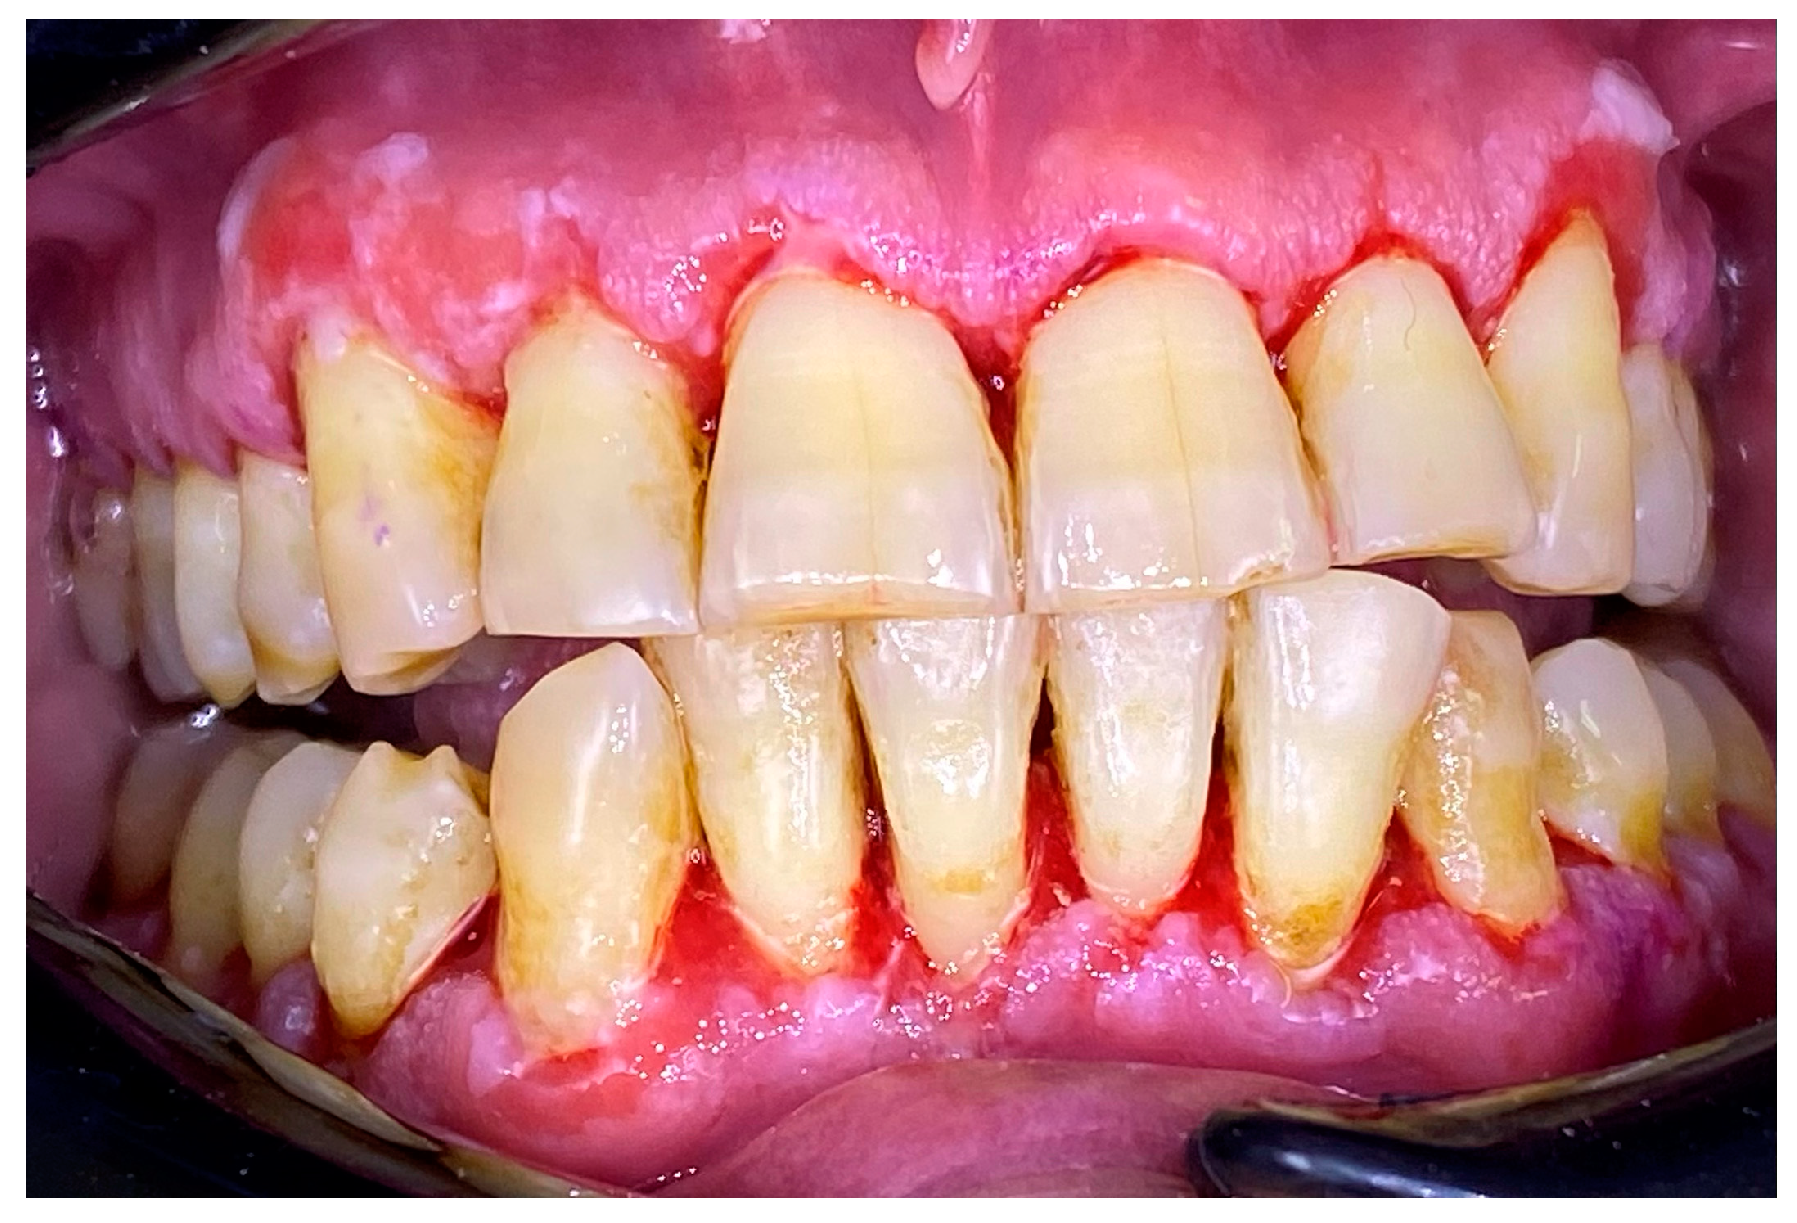

2.1. Clinical Case 1—Mucous Membrane Pemphigoid (MMP)